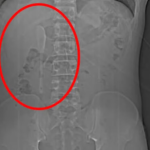

VÍDEO: Mulher é internada após plug anal ficar preso no intestino e médico faz alerta

Médico alerta para riscos do uso inadequado de acessórios íntimos e explica como evitar acidentes.